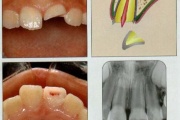

Alveolaarjätke murd